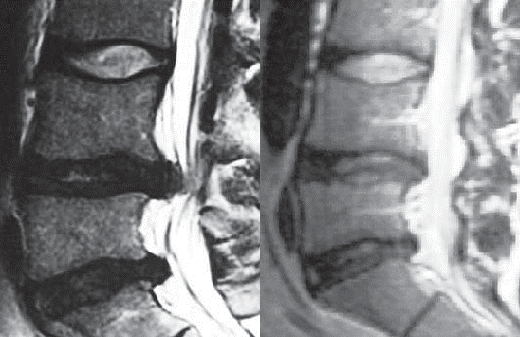

Иллюстрация 2

На левом снимке поясничного отдела позвоночника: грыжа межпозвонкового диска в сегменте LIV–LV, спондилёз, эпидурит, арахноидит. Грыжа межпозвонкового диска в сегменте LV–SI.

На правом снимке состояние поясничного отдела позвоночника после 8 курсов УБР.